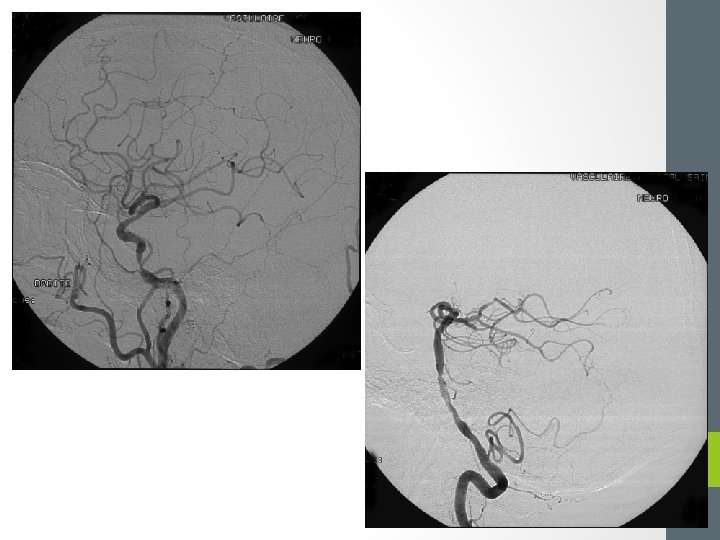

Bilan vasculaire • Vaisseaux du cou et intracérébraux: • • Échodoppler Angioscanner Angio IRM Angiographie conventionelle

Bilan étiologique • Imagerie cérébrale en urgence • Si hématome sur hypertension • Bilan d’HTA (échographie cardiaque) • Si lésion sous jacente • Artériographie…

• Définition • Constitution d’un hématome intracérébral = environ 15% des AVC • Mécanismes • Rupture artérielle : d’un anévrisme artériel ou d’une MAV • Saignement : d’une tumeur ou d’une métastase • Poussée hypertensive 81

Plusieurs mécanismes possibles • Origine cardiaque (embolie) • Origine artérielle (athérome, dissection, sténose) Athérome (Diabète, cholestérol, HTA, tabac) Cardioembolique (fibrillation auriculaire+++) Dissection